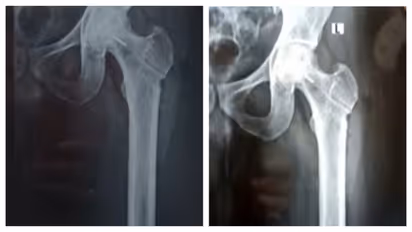

തിരുവനന്തപുരം: തിരുവനന്തപുരം ജൂബിലി മെമ്മോറിയൽ ആശുപത്രിക്കെതിരെ ഗുരുതര ചികിത്സാപിഴവ് പരാതി. ഇടുപ്പ് എല്ലിൽ ശസ്ത്രക്രിയ ചെയ്യുന്നതിനിടെയാണ് ചികിത്സ പിഴവുണ്ടായിരിക്കുന്നത്. രക്തയോട്ടം കൂട്ടാനുള്ള ശസ്ത്രക്രിയക്കിടെ ഡ്രിൽ ബിറ്റ് ഒടിഞ്ഞു കയറുകയായിരുന്നു. മലയിൻകീഴ് സ്വദേശി ജിജിൻ ജോസിൻെറ ഇടത് ഇടുപ്പ് എല്ലിലാണ് ഡ്രിൽ ബിറ്റ് ഒടിഞ്ഞു കയറിയത്. ജിജിൻെറ പരാതിയിൽ കൻോൺമെന്റ് പൊലീസ് കേസെടുത്തിട്ടുണ്ട്. ലോഹ കഷണം നീക്കം ചെയ്യാനാകില്ലെന്നും ലോഹ കഷണം ഇരിക്കുന്നതിനാൽ പ്രശ്നങ്ങളുണ്ടാകില്ലെന്നും രോഗിയെ അറിയിച്ചതാണെന്ന് ആശുപത്രി അധികൃതർ വ്യക്തമാക്കുന്നു.